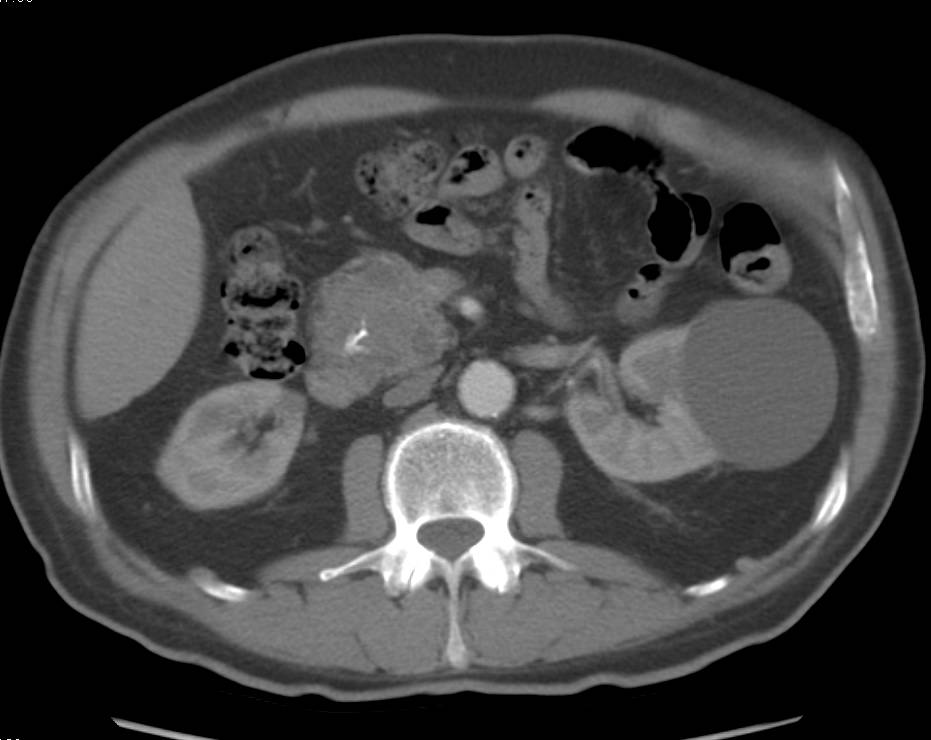

Neuroendocrine Tumor Near the Pancreas